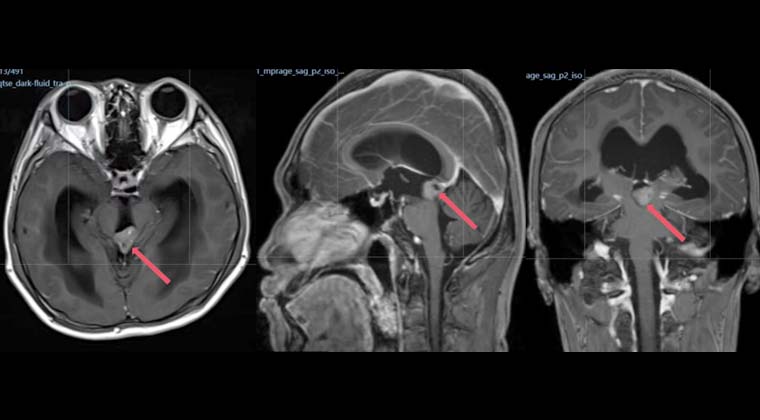

Мальчик-подросток, 13 лет

Герминальная опухоль шишковидной железы

Месяц назад у пациента появились головные боли в школе без явной причины. Сначала их не воспринимали всерьёз, затем головные боли постепенно усиливались и сопровождались нарушением походки. Семья обратилась за медицинской помощью. МРТ головного мозга показало образование в шишковидной железе с обструктивной гидроцефалией. Анализы крови выявили умеренно повышенный уровень HCG при нормальных показателях AFP. Клинический диагноз: чистая герминальная опухоль шишковидной железы.

Была проведена прецизионная радиотерапия в дозе 9 Гр/5 фракций. Опухоль шишковидной железы значительно уменьшилась в размере (красная стрелка на изображении указывает на опухоль), гидроцефалия улучшилась, головные боли практически исчезли, походка улучшилась. В дальнейшем лечение проводилось по стандартной схеме химиорадиотерапи для внутричерепных герминальных опухолей.

До лечения

5 сеансов лучевой терапии